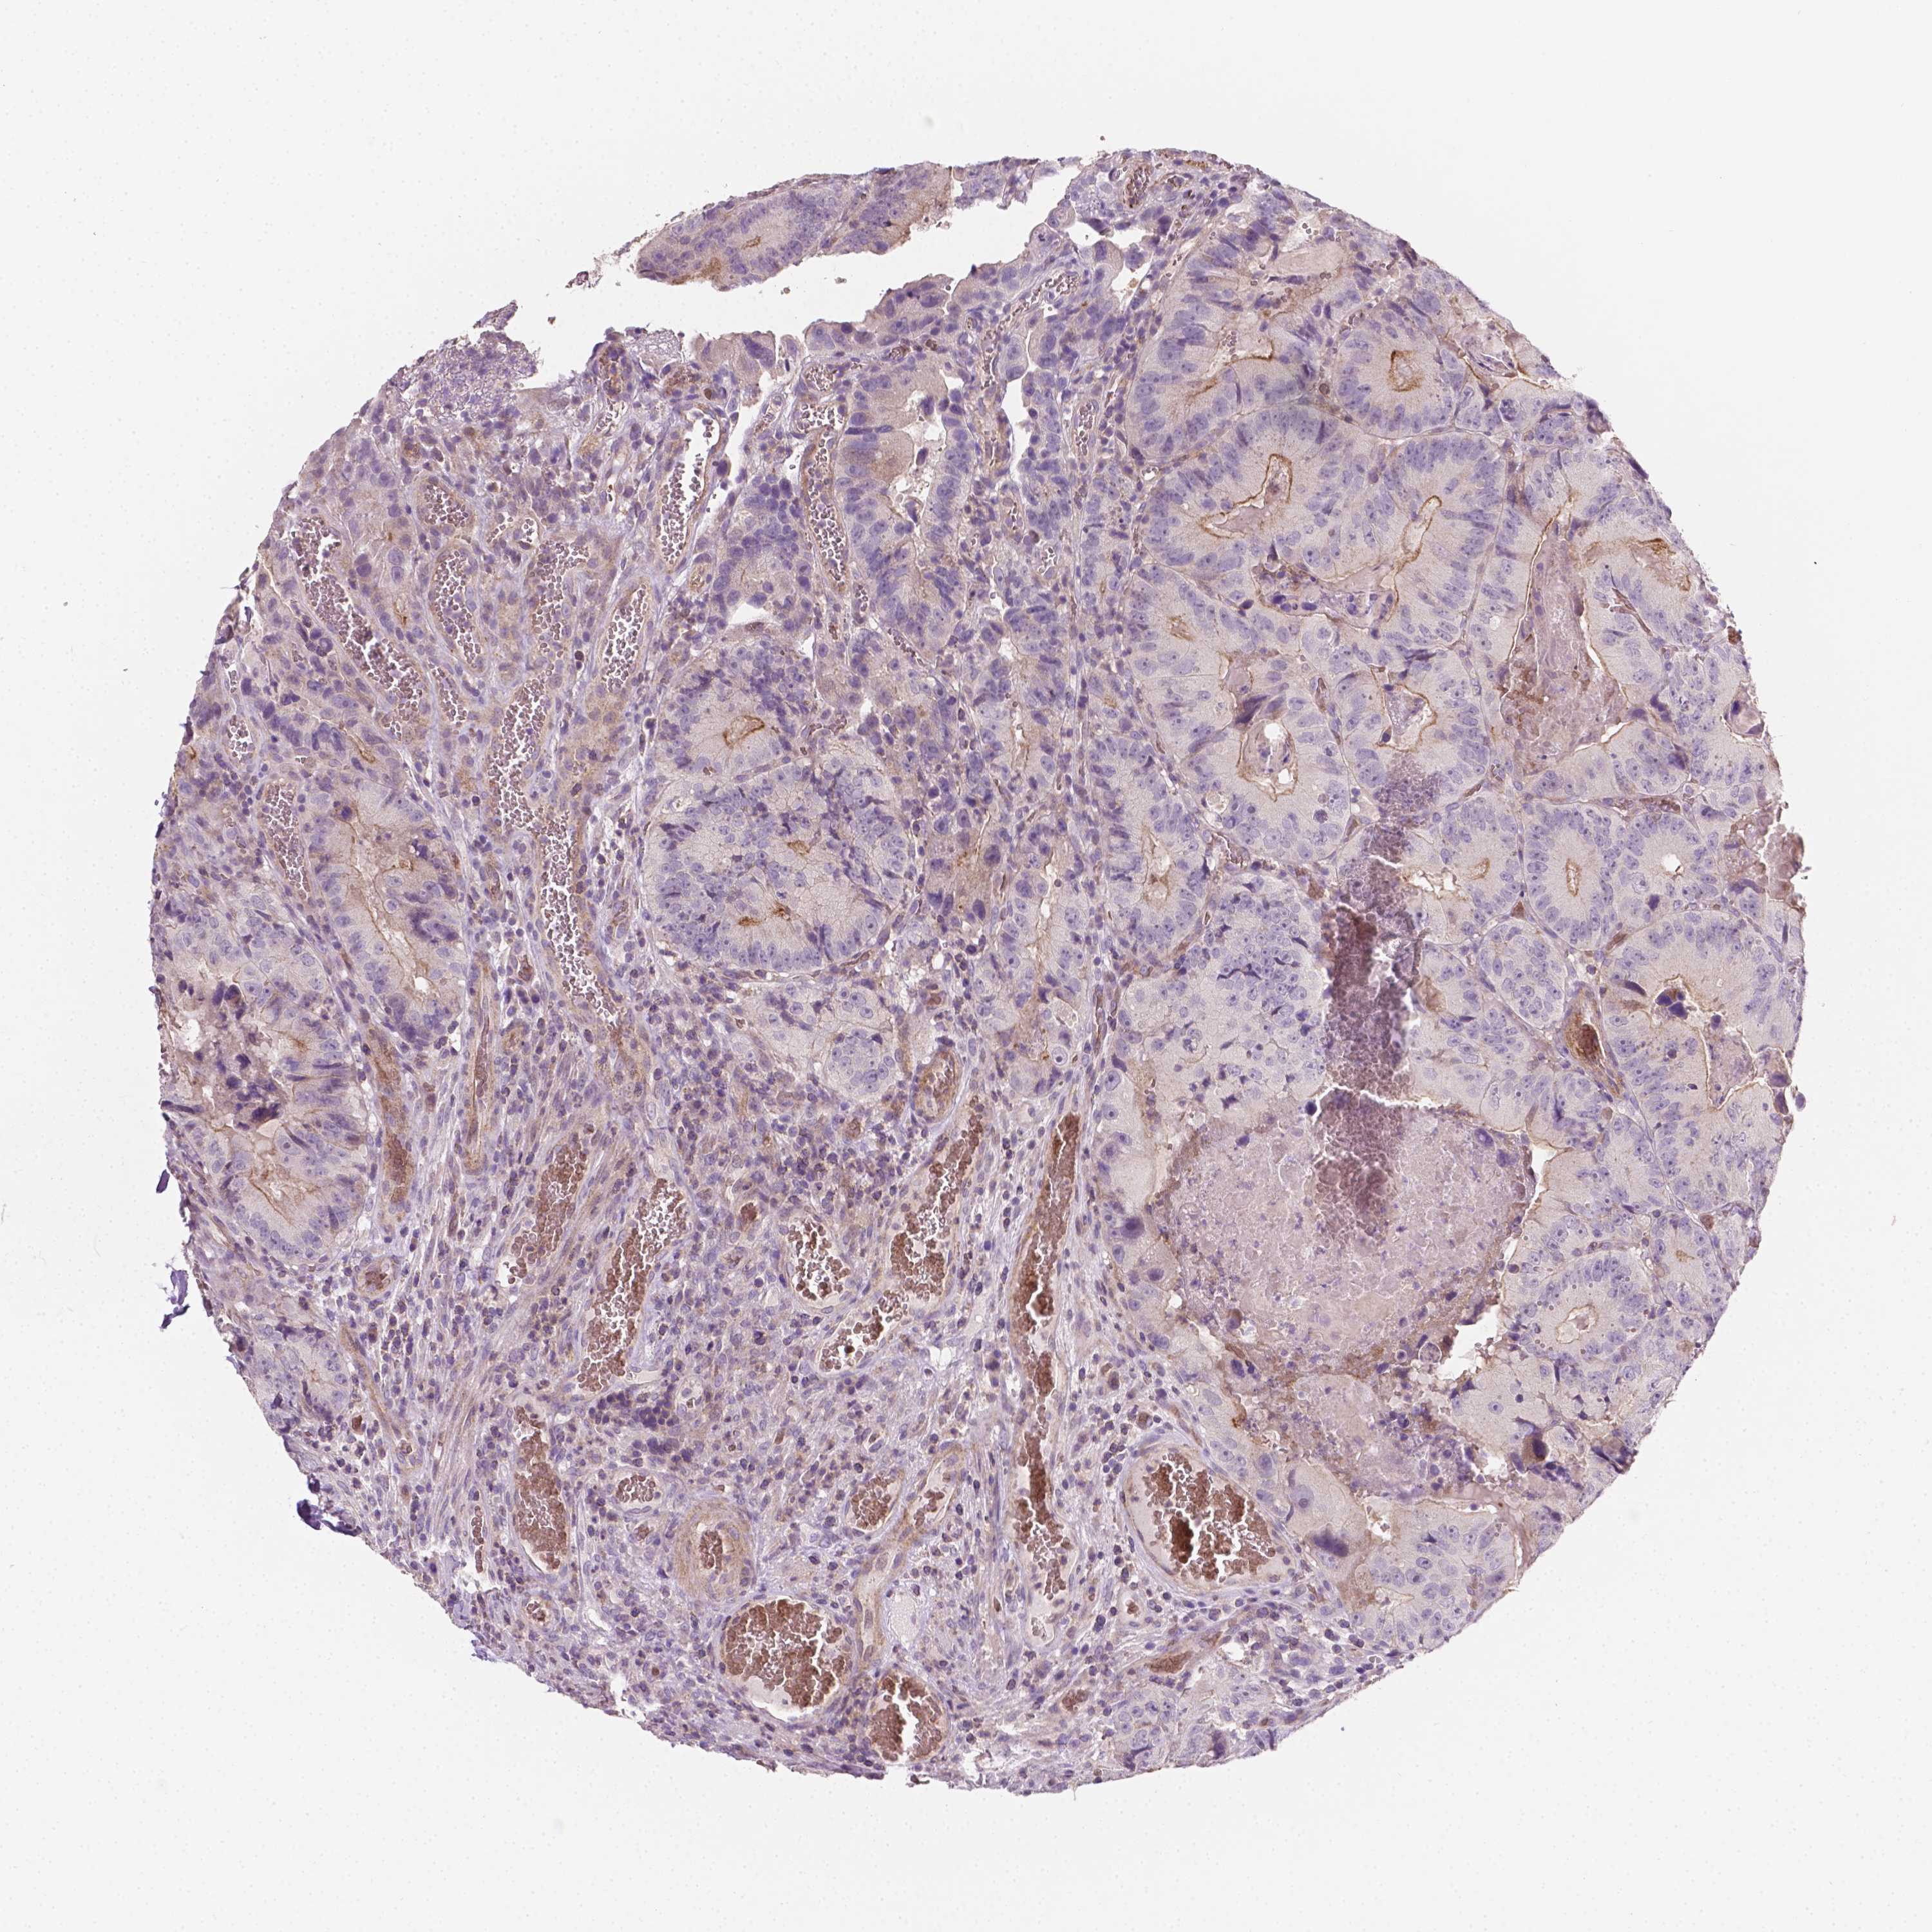

CANCER COLORECTAL CANCER Show tissue menu

Colorectal cancer

Human cancer

Colon adenocarcinoma